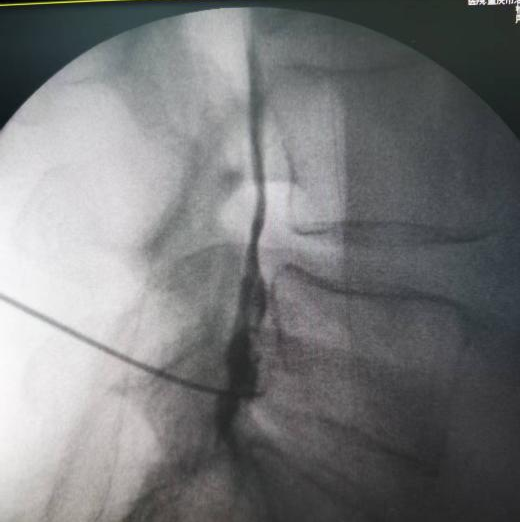

(二)椎间盘化学髓核溶解术

向突出椎间盘周围注射胶原酶,促使病变部分变性软化,最终经人体代谢吸收,从根源治愈腰椎间盘突出症。